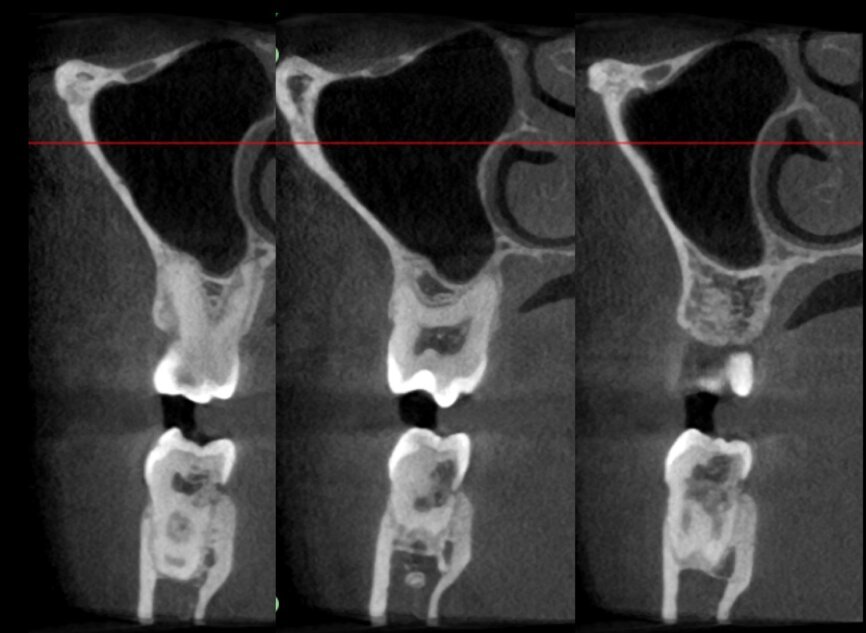

The case with which I would like to start my clinical review is a perfect example of how difficult it is to establish the origin of the patient’s symptoms on the basis of an intraoral radiograph alone. Not only does the 2D study fail to establish with certainty the presence of a lesion, but more importantly, it is impossible to establish the size, morphology and type of the lesion. An analysis of the 3D imaging, however, provides a clear picture of the clinical situation: the coronal and sagittal slices revealed the presence of a large lesion extending from the apex of the mesial root of this molar to the furcation, while the axial slices allow us to conduct a precise analysis of the endodontic anatomy and, in particular, the shape of the mesial root, which in this case was fused with the palatine root. A full overview of the case can, therefore, guide the decision-making process and direct the treatment plan towards a specific type of treatment (Figs. 1–4).